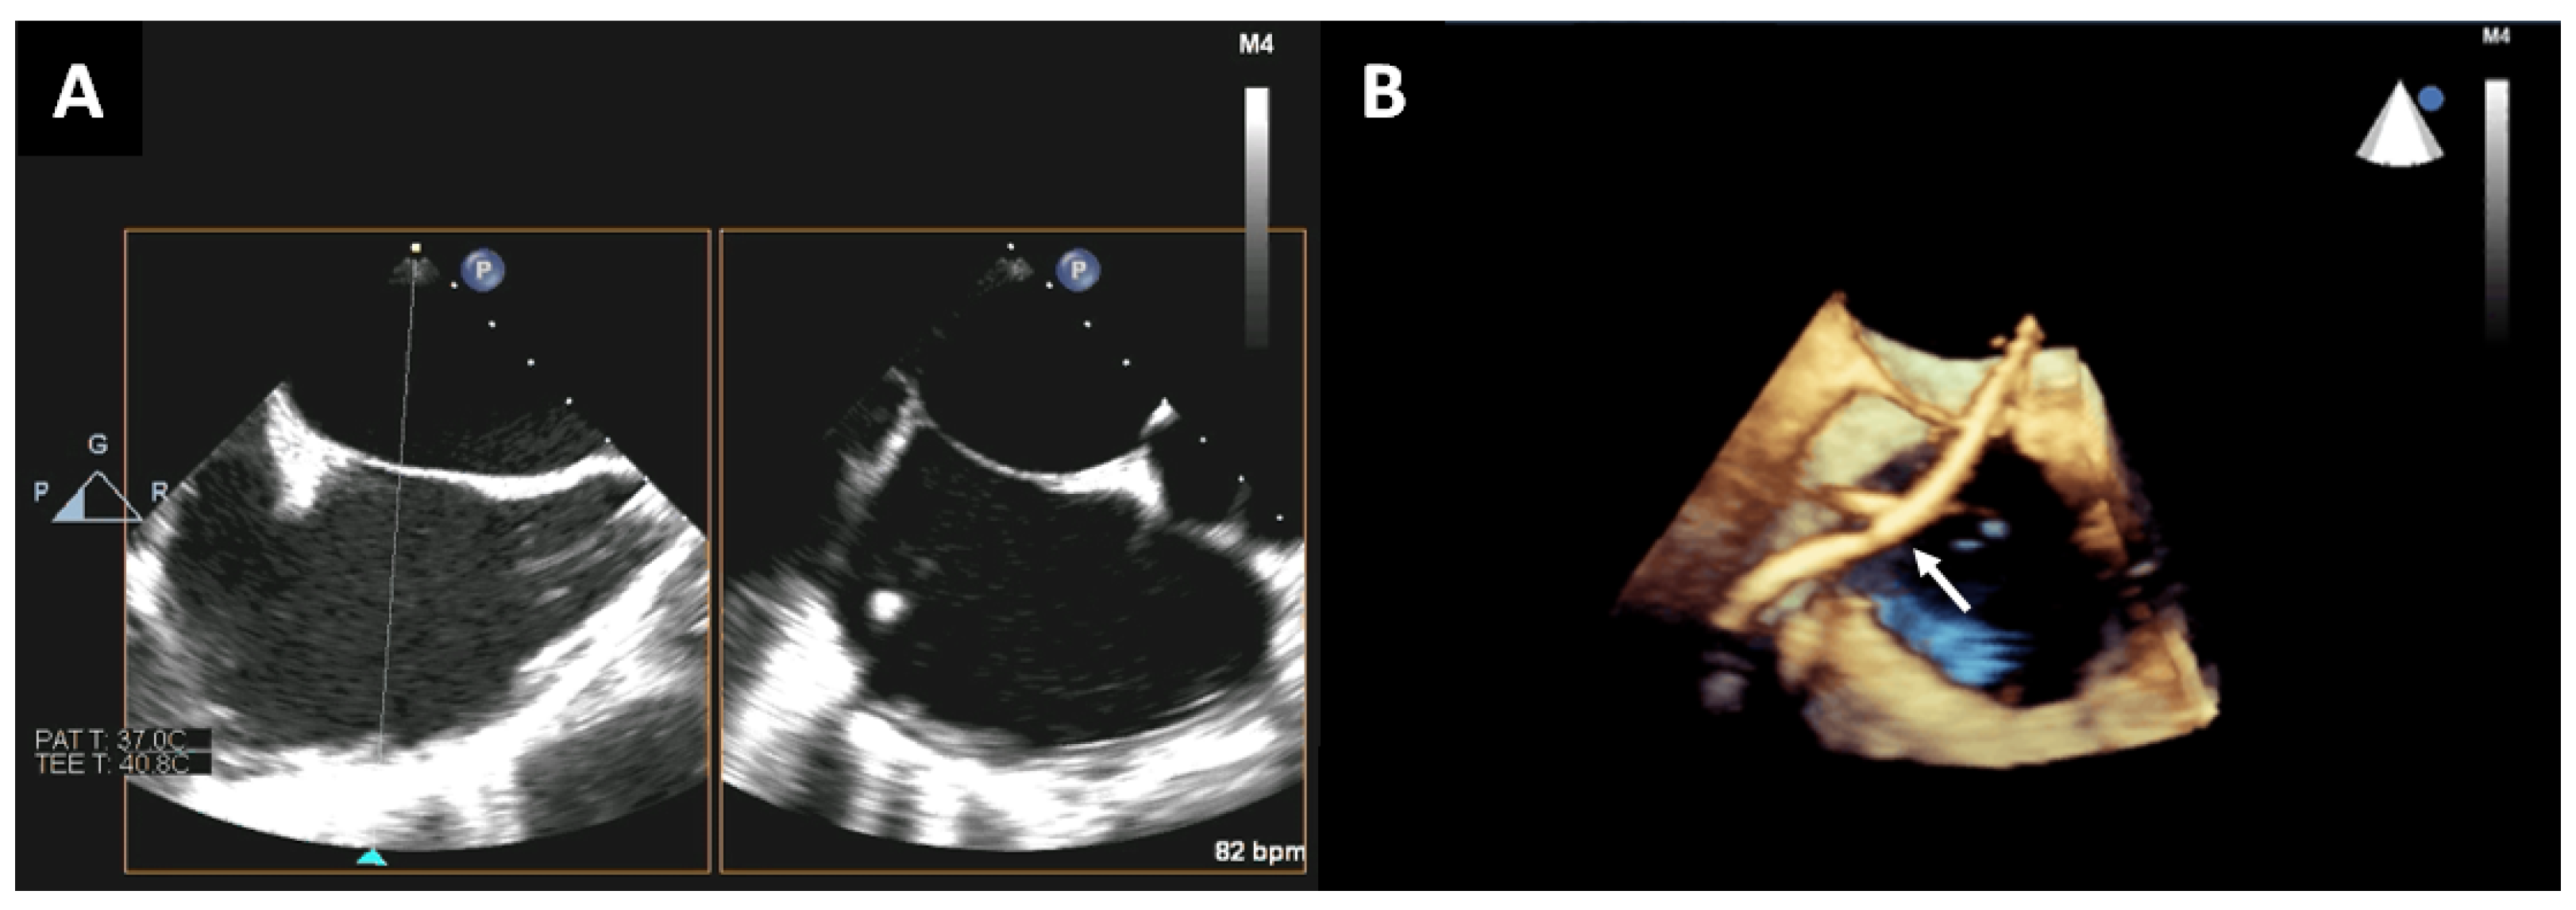

2. Trans-Septal Puncture